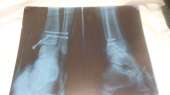

IMG201611181702[...].jpg (253Кб, 1280x720)

ЧТО-ТО ЩЕЛКАЕТ В ЛОДЫЖКЕ

@

И СТОПА ЧТО-ТО БОЛТАЕТСЯ

НАВЕРНОЕ КОСТИ РАЗНОСИЛИСЬ

ВКРУЧИВАЕШЬ САМОРЕЗ

ВСЕ РАВНО БОЛТАЕТСЯ

ВКРУЧИВАЕШЬ ЕЩЕ ТРИ

ВОТ ТЕПЕРЬ ЗАЕБИСЬ

>>140431171

больше шурупов богу шурупов!

>>140443070

саморезов, гуманитарий епта